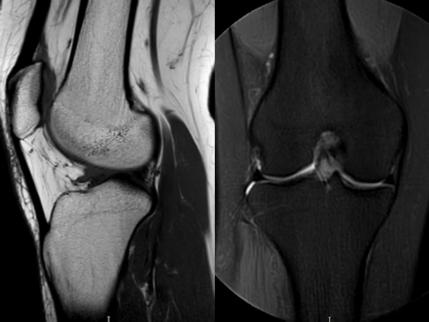

5.27“我愛膝”特別企劃 ——膝關節磁共振:為您的“人體軸承”做一次高清體檢

MRI偵查:精準捕捉半月板撕裂或變性(半月板內高信號),避免拖成“關節

(半月板撕裂)

MRI偵查:揪出前交叉韌帶斷裂“波浪狀”或連續性中斷)、內側副韌帶損傷,防止關節“脫軌”

內側副韌帶損傷)